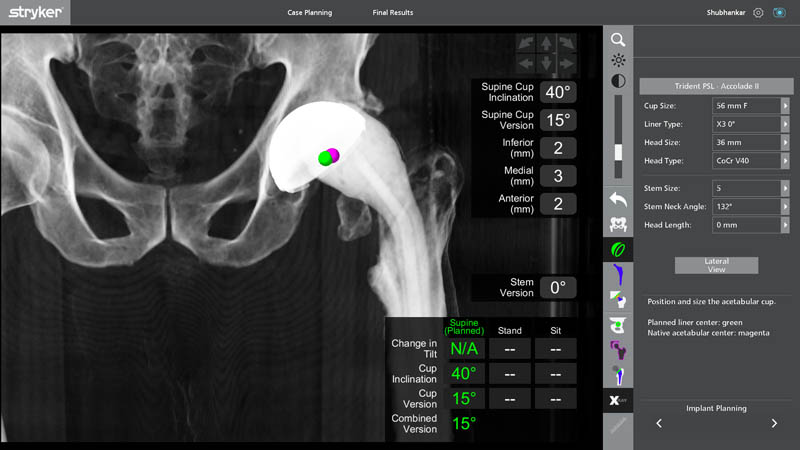

Preoperative Planning

- Precise Implant Positioning

Segmentation is an advanced imaging and planning process where CT-based data is converted into highly detailed 3D anatomical models. This allows the surgeon to:

- Customize implant size and placement